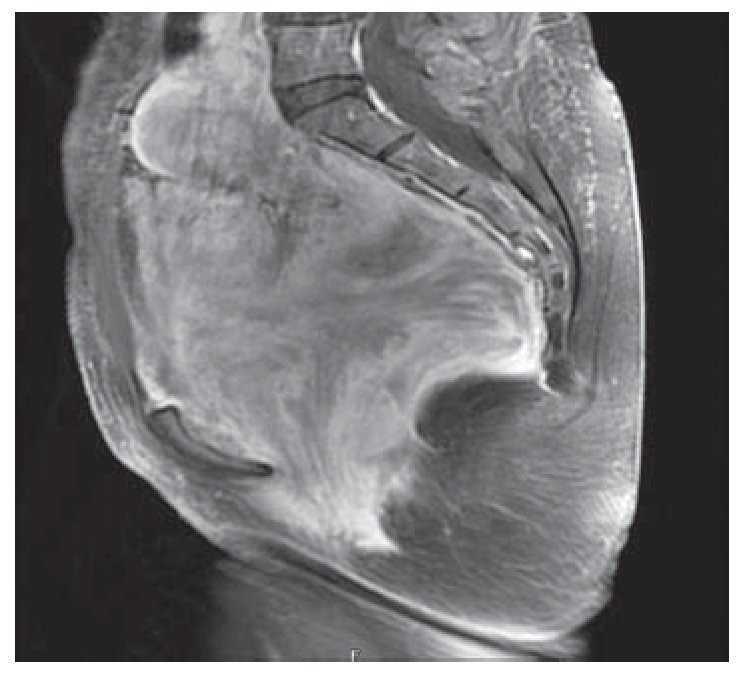

Mujer de 41 años de edad, sin antecedentes, que consultó por historia de dolor pélvico difuso, de baja intensidad, no irradiado, de ocho meses de evolución. Al examen físico se encontró una masa adherida a planos profundos y poco dolorosa a la palpación. Se le realizó una tomografía computadorizada que informó una extensa neoplasia pélvica de características malignas, que se extendía hasta el espacio isquiorectal, con desplazamiento y compresión de la vejiga y el útero, además de escaso líquido alrededor de la lesión (Figura 1). Se realizó una resonancia magnética nuclear que demostró una lesión de 14 x 14 cm, posiblemente de origen lipomatoso con degeneración mixoideangiolipomatosa, con probable infiltración al recto y sigmoides, dilatación pielo-ureteral bilateral por obstrucción del tercio distal de los uréteres (Figuras 2 y 3). Se realizó una colonoscopia que sólo evidenció desplazamiento del sigmoides por compresión extrínseca. Se le realizó una laparotomía exploratoria encontrando una masa pélvica de 15 x 20 cm, la cual se pudo separar de las estructuras adyacentes y resecar en su totalidad. El reporte histopatológico fue de una masa de 15 x 18 cm, con un peso de 260 g, de color amarillo-gris liso y opaco, de aspecto nodular y consistencia blanda. Al corte se encontraron áreas quísticas compatibles con angiomixoma (Figura 4). La paciente presentó una evolución satisfactoria, se le dio egreso. Actualmente se encuentra asintomática y sin datos de recurrencia.

Figura 3. Tomografía computadorizada que mostró masa con infiltración al recto sigmoides